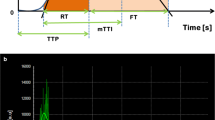

Top: Representative images and quantification of trichrome staining from contralateral medulla. SW ameliorated the increased medullary fibrosis in ARAS CLK. Bottom: Representative MRE images (yellow/red color indicates greater stiffness) from contralateral cortex and medulla (TIFF 2309 kb)